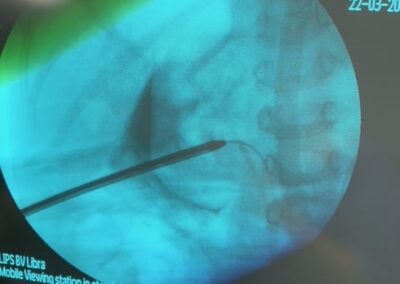

Ο Δρ. Βασίλης Πουλάκης ήταν πάλι όπως κάθε μήνα και τον μήνα Μάρτιο για δύο ημέρες (Δευτέρα 22 και Τρίτη 23 Μαρτίου 2021) στο Ιπποκράτειο Νοσοκομείο στη Λευκωσία της Κύπρου, όπου πραγματοποίησε τέσσερεις ρομποτικές ριζικές προστατεκτομές με διατήρηση των αγγειονευρωδών δεματιών της στύσης και παράλληλα με εκτεταμένο λεμφαδενικό καθαρισμό αλλά και μία αμφοτερόπλευρη διαδερμική νεφρολιθοτριψία (Ultra-Mini PCNL) σε ένα μικρό αγόρι ηλικίας 3,5 ετών με κοραλλοειδείς λίθους και στους δύο νεφρούς.

Η πρωτοποριακή και μοναδική για τα ουρολογικά χρονικά της Κύπρου εξαιρετικά λεπτεπίλεπτη διαδερμική αφαίρεση των ευμεγέθων λίθων και από τους δύο νεφρούς του μικρού αγοριού με μία μόνο επέμβαση-νάρκωση ήταν απολύτως επιτυχής και ο μικρός ασθενής κατέστη ελεύθερος λίθων (“stone free”).

Για την επιτυχή πορεία αυτής της πολύπλοκης και δύσκολης επέμβασης θα ήθελα να ευχαριστήσω όλους όσους, επώνυμα και ανώνυμα, βοήθησαν αλλά κυρίως τους συνεργάτες μου Ουρολόγους, Βασίλη και Νίκο που με στήριξαν σε κάθε βήμα αυτής της περίπλοκης επέμβασης.Παρακάτω οι φωτογραφίες από την ακτινοσκόπηση την ώρα της επέμβασης και η τελική εικόνα με τις νεφροστομίες.